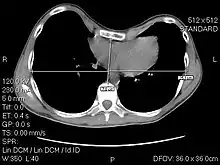

A CT scan showing a 3.58 index

The Haller index, created in 1987 by J. Alex Haller, S. S. Kramer, and S. A. Lietman,[1] is a mathematical relationship that exists in a human chest section observed with a CT scan. It is defined as the ratio of the transverse diameter (the horizontal distance of the inside of the ribcage) and the anteroposterior diameter (the shortest distance between the vertebrae and sternum).[2]

A normal Haller index should be about 2.5. Chest wall deformities such as pectus excavatum can cause the sternum to invert, thus increasing the index.[6][7] In severe asymmetric cases, where the sternum dips below the level of the vertebra, the index can be a negative value.[8]